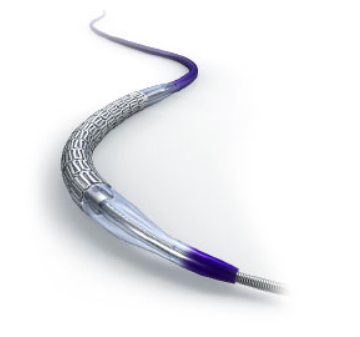

Coronary Drug Eluting Stents

Drug-eluting stents are designed to keep coronary arteries open while slowly releasing medication to prevent restenosis. They combine reliable scaffolding with advanced drug technology to improve long-term vessel patency and support successful percutaneous coronary interventions (PCI).

Drug-eluting stents are designed to keep coronary arteries open while slowly releasing medication to prevent restenosis. They combine reliable scaffolding with advanced drug technology to improve long-term vessel patency and support successful percutaneous coronary interventions (PCI).